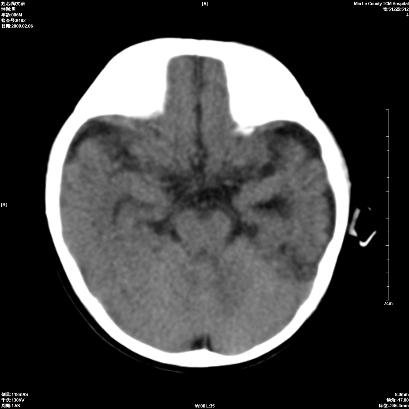

以下是引用wxq2008在2009-2-6 17:01:00的发言:[br]hie后遗症脑萎缩。

以下是引用学医在2009-2-6 21:45:00的发言:[br]hie后遗改变